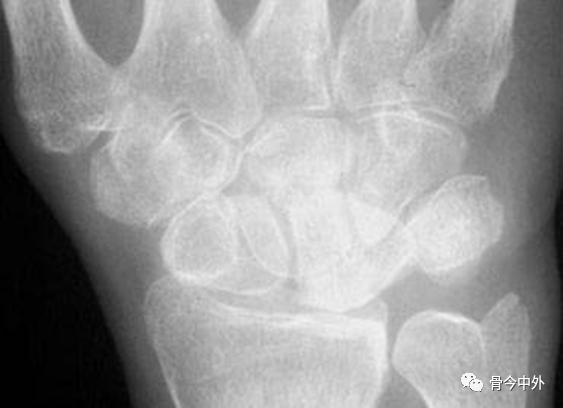

图1 成人期腕关节正侧位及舟骨蝶位片。1.舟骨;2.月骨;3.三角骨;4.豆状骨;5.大多角骨;6.小多角骨;7.头状骨;8.钩骨;9.桡骨茎突;10.尺骨茎突;11.第一掌骨基部。